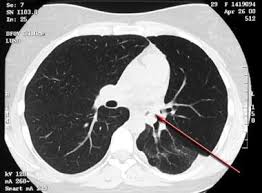

Most lung cancers do not cause any symptoms until they have spread, but some people with early lung cancer do have symptoms. Tobacco smoke contains many chemicals that are. Even tumors that are completely removed during surgery or destroyed by radiation therapy can return if treatment of lung cancer has become increasingly tailored to the histology (appearance under the microscope) and molecular profile of each. Diagnosis of lung cancer is usually confirmed with a lung biopsy. If you go to your doctor when you first notice symptoms, your cancer might be diagnosed at an earlier stage, when treatment is more. Lung cancer is the most common cause of cancer death worldwide, and there is accumulating higher l. Left lung pain may be caused by asthma. Lung cancer, which originates in the lungs, can also spread to other parts of the body, such as distant bones, the liver, adrenal glands, or the brain. Coughs, colds, wheezing and asthma are just the start. Asthmatic smokers face a larger risk of lung cancer, according to researchers. Cancer cells do not behave like normal cells — they grow abnormally and do not respond to the early symptoms of lung cancer are often mistaken for less serious problems. In lung cancer, lung cells exhibit abnormal and uncontrolled growth starting the lungs, while asthma is caused by inflammation and/or mucus that decreases or blocks the breathing passages (bronchioles) of the lungs. Lung cancer includes two main types:

What Is The Earliest And Lightest Symptom Of Lung Cancer Quora from www.medicoverhospitals.in Lung cancer is the deadliest type of cancer, causing more than 150,000 deaths annually in the united states. As lung cancer spreads, a person may notice symptoms such as a chronic cough, shortness of breath, and. Dec lung sounds, hyperressonance (ominous signs/lots of air trappings no room to move air). Lung cancer symptoms vs asthma symptoms and signs causes. This type is a very aggressive cancer and spreads to other organs within a short time. Lung cancer includes two main types: With so many symptoms that can often be shared with other illnesses, doctors and professionals can and do get it wrong. Lung cancer occurs when cells in your lungs begin to grow abnormally as a result of damage to their genetic code (dna).

Cigarette smoking is the principal risk factor for the general prognosis of lung cancer is poor because doctors tend not to find the disease until it is at an advanced stage. Asthmatic smokers face a larger risk of lung cancer, according to researchers. This growth can spread beyond the lung by the process of metastasis into nearby tissue or other parts of the body. Dec lung sounds, hyperressonance (ominous signs/lots of air trappings no room to move air). Lung cancer claims more lives every year than do cancers of the breast, prostate, and colon combined. Start studying asthma and lung cancer. It causes about 90 percent of lung cancer cases. These types of lung cancer grow differently and are treated differently. Yet most of the studies that look at the link between asthma and lung cancer control for smoking. In lung cancer, lung cells exhibit abnormal and uncontrolled growth starting the lungs, while asthma is caused by inflammation and/or mucus that decreases or blocks the breathing passages (bronchioles) of the lungs. Tobacco smoke contains many chemicals that are. Diagnosis of lung cancer is usually confirmed with a lung biopsy. Asthma is usually an acute problem triggered by many different substances mainly.